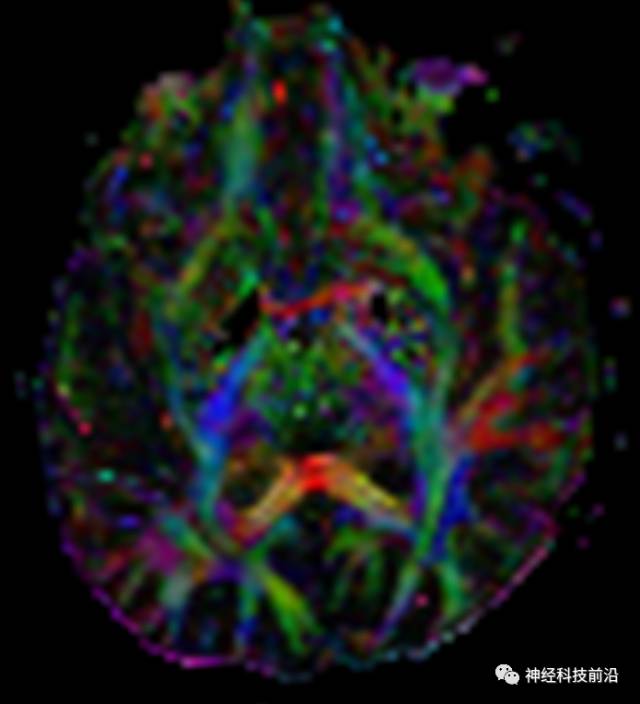

皮质脊髓束与皮质脑桥束的关系毗邻

脑干内高信号为一近环形纤维束,其作用尚待研究。

上述纤维束与小脑中脚的位置毗邻

终上所述:脑干高信号为一近环形纤维束,内囊后肢高信号为皮质脑桥束,皮质脊髓束在中脑位置略靠后。高信号位于中脑前缘,是皮质脑桥束的位置所在,另外有部分桥连纤维。